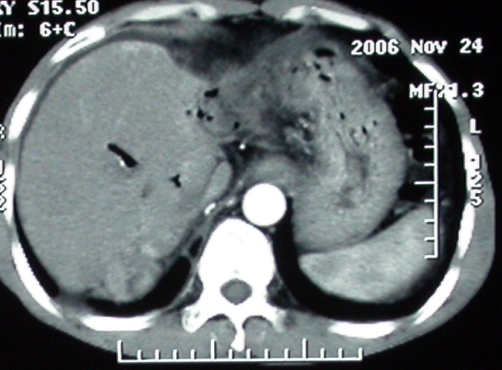

标题: 上腹隐痛、饱胀、消瘦2-月。

增强ct所见【动脉增强期】

门脉主干及肠系膜上静脉近端明显增粗,尤其前者呈等低混杂密度,增强后周围见轻度环形强化。明显占位效应。肝内外胆管见大量气体影。胆囊明显增大。

考虑:1、门脉栓塞; 2、肝内外胆管积气。